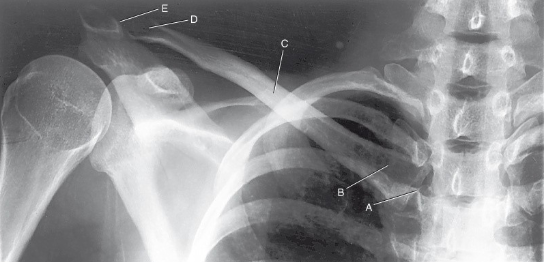

label the anatomy accordingly A-E, the projection/part, and rotation if applicable

sternoclavicular joint, sternal extremity, body, acromial extremity, acromioclavicular joint

AP clavicle

acromion, coracoid process, inferior angle, spine of scapula, body of scapula

PA oblique